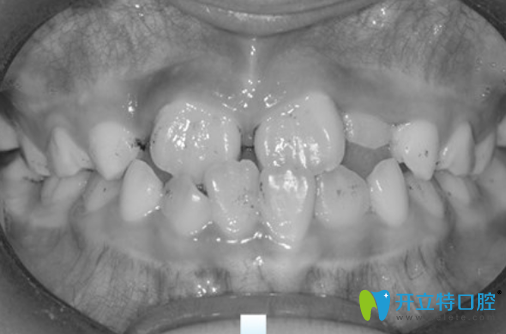

7歲兒子地包天沒有做矯正前樣子:

好在去成都金琴口腔時(shí)許院長給了我信心,告訴我孩子正處于替牙期,正是牙齒矯正的黃金時(shí)期,現(xiàn)在矯正有利于孩子下頜骨的發(fā)育,只要孩子配合矯正,一般是沒有問題的。